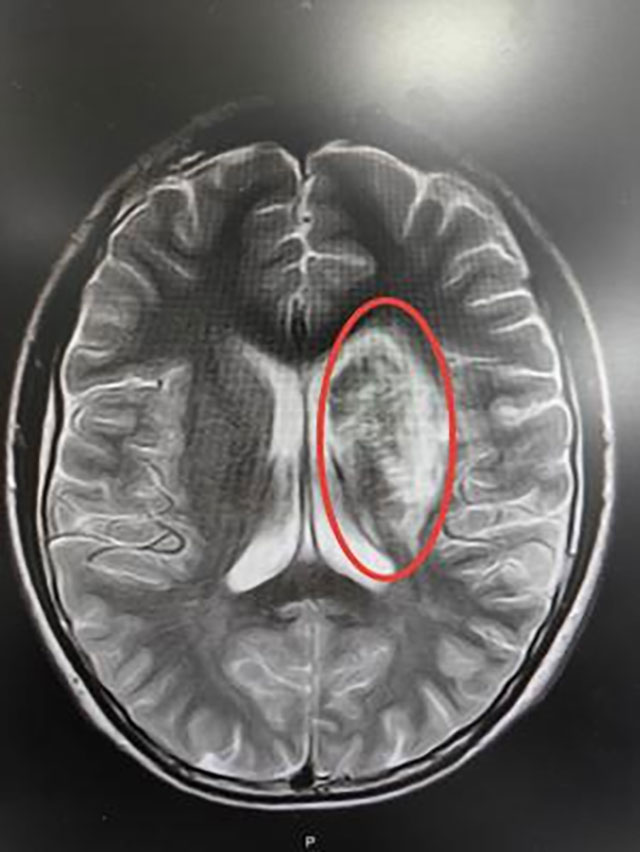

●头颅增强MRI:左侧额顶颞岛叶、基底节区、侧脑室旁及大脑中脚异常信号,部分病灶弥散受限,左侧外囊软化表现;

头颅MRI影像表现

最后考虑诊断为卵圆孔未闭合所致的脑梗死(心源性栓塞型),经中西医结合治疗后小王同学好转出院,并拟于后期接受卵圆孔未闭封堵术治疗。